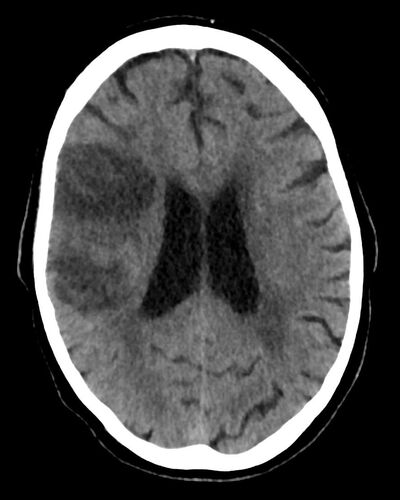

Bei Verdacht auf einen Schlaganfall zum Beispiel zählt jede Minute. Wichtig ist vor allem, schnell zu differenzieren, ob ein verschlossenes Blutgefäß die Symptome verursacht oder eine Hirnblutung. „Die Symptome sind in beiden Fällen ähnlich, die Konsequenzen aber ganz andere“, betont Glüer. Im ersten Fall muss die Durchblutung des betroffenen Gehirnbereichs durch Gabe spezieller Medikamente schnellstmöglich wiederhergestellt werden. Im zweiten Fall muss die Blutung gestoppt und Schädigungen durch das austretende Blut müssen vermieden werden.

CT-Aufnahmen des Gehirns von Personen mit Schlaganfall: Hirnblutung. © Klinik für Radiologie und Neuroradiologie -